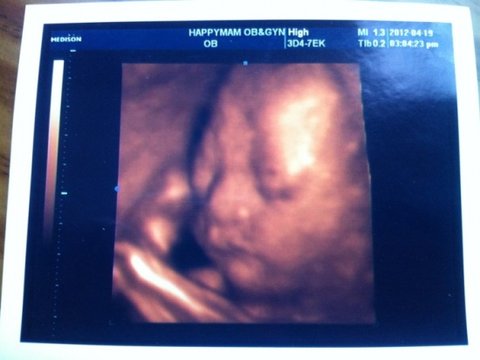

하균이 입체 초음파 사진이예여~